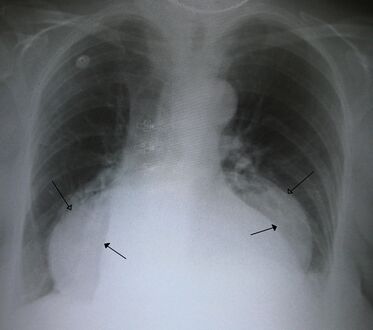

فتق حجابي كبير في صورة للصدر بالأشعة السينية، حيث يُميز بأسهم مفتوحة على النقيض من حدود القلب التي تتميز بأسهم مغلقة.

يتم تشخيص الفتق الحجابي هذا بشكل أساسي من خلال مستوى الهواء والسائل (الموضح بواسطة الأسهم).